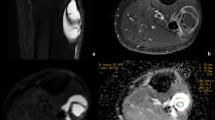

Soft tissue sarcomas are rare neoplasms of mesenchymal origin. They constitute less than 1 % of all malignant tumors, with an incidence increasing slightly with age [2]. Unfortunately, for the majority, conventional MRI is incapable to provide a precise histologic diagnosis (Fig. 55.1) and also to determine the extent of tumor necrosis that is essential to analyze response to treatment [1].

Synovial sarcoma of the abdominal wall. (a) Axial T1 fat-suppressed MR image shows a hyperintense lesion in the soft tissue of the abdominal wall (arrow). Axial DWI (b) and ADC map (c) images show restricted diffusion (white arrows) of the lesion, with ADC = 0.98 × 10−3 mm/s2, suggesting malignant tissue. (d) The tumor has a type IV curve with washout phase (yellow dotted line) on MR perfusion imaging, indicating that it enhances early at the same time as the artery. The red type IV curve indicates the artery